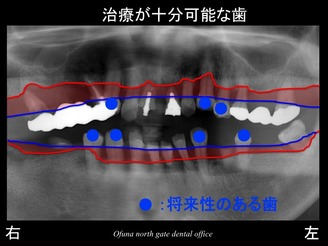

逆に治療が可能な歯は以下の歯です。

歯周病治療、虫歯の治療…等を行うことにより治療が可能な歯です。